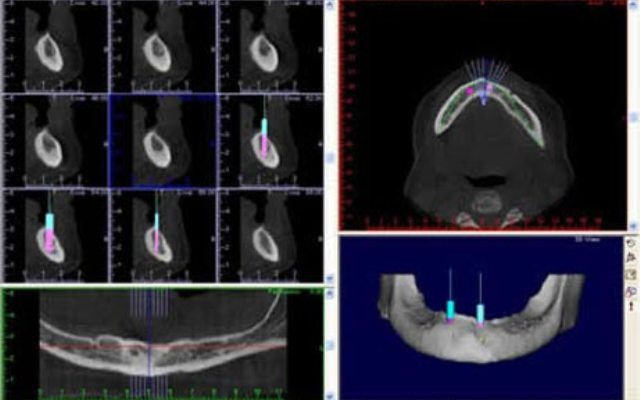

Reformatação computadorizada com DentalSlice

Para trabalhar no DentalSlice basta solicitar na Clinica Serraro a tomografia computadorizada, onde as imagens DICOM (arquivos da tomografia) serão convertidas para o ambiente DentalSlice criando um arquivo que será enviado para o cirurgião dentista.

O Dental Slice é uma ferramenta de planejamento implantodôntico pré-operatório, desenhado para oferecer auxílio cirúrgico-protético com alto nível de precisão e aumentar a margem de segurança no tratamento.

O programa foi projetado para rodar em  computadores pessoais e ambiente Windows.

O programa é acessível a qualquer cirurgião dentista e permite que o  planejamento seja realizado pela própria  equipe que vai realizar a cirurgia.  As imagens também podem ser segmentadas, oferecendo melhor visualização de detalhes, como por exemplo do seio maxilar, canal da mandíbula ou de lesões.